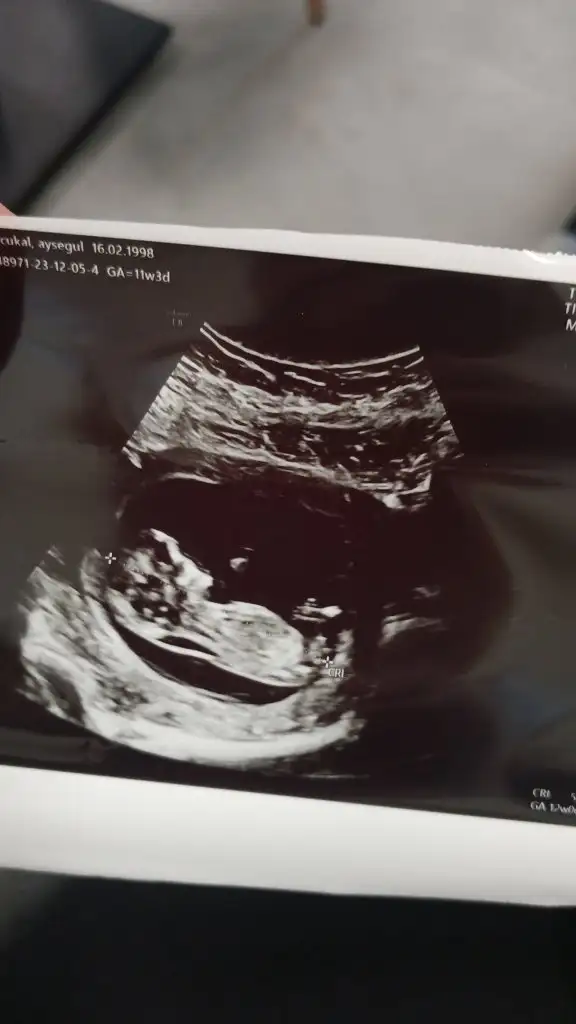

Bu gun ultrasona girdik 11 haftalik hamileyim bebegin boy kilo doktor dedigni unuttum ultrason da hangisi boy kilo bilen varmi

yagmurcicegii Gırnatacı küpek Üyelik İptali Anneler Kulübü Kayıtlı Üye 15 Ocak 2023 3.893 4.773 53 5 Aralık 2023 Konu Sahibi Konu Sahibi ay550 #2 Boyu ve kilosu daha bakılmıyor